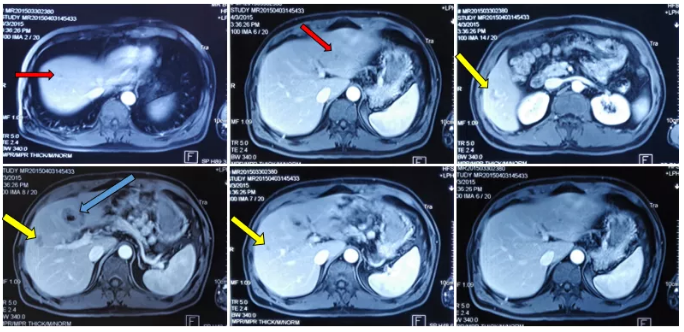

MRI检查结果:肝脏多发异常信号影,多为转移瘤。

肝脏MRI检查

MRI复查结果:疗效评价PR(靶病灶缩小32%)。

化疗前后病灶变化情况

术后MRI复查:

病灶变化情况

MRI复查结果: